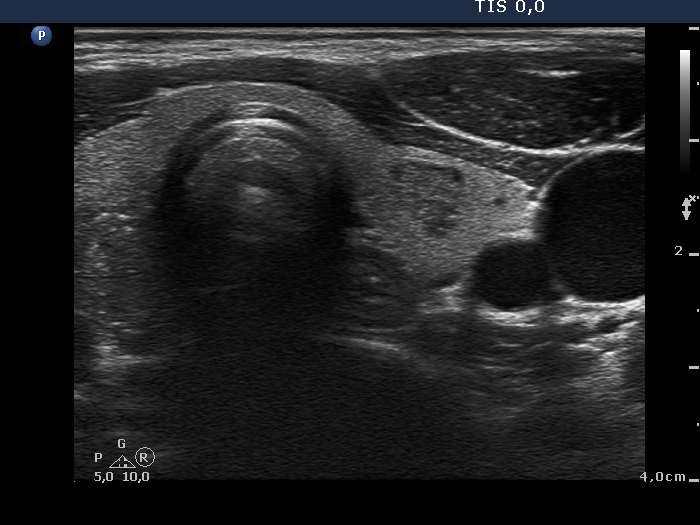

100 consecutive patients with papillary carcinoma - Case 2. (ultrasonographic picture 6)

Left lobe, horizontal view. There is a small, moderately hypoechogenic nodule in the central part of the lobe. It is worth to compare the non-specific intranodular granulations of the benign lesion with the brightet granules of the papillary carcinoma. A small part of the cancer can be seen left in the image.